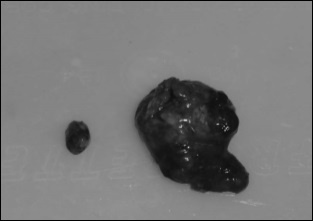

The tumours in the walnut group were smaller than those in the other group.

The photo below shows on the left a typical prostate cancer tumour that the researchers found in the walnut diet group, and on the right the biggest tumour in the mice that did not get walnuts.